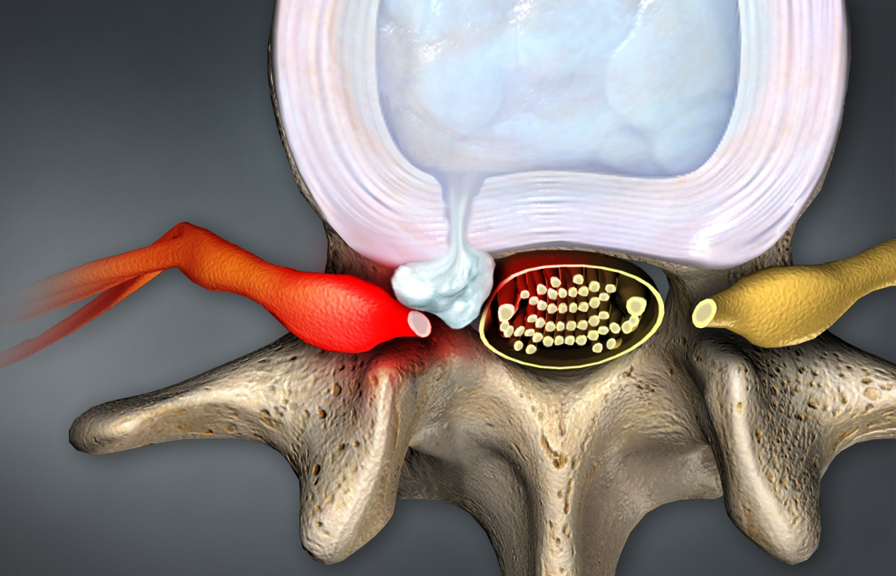

- Spinal Stenosis

- Pinched Nerves

- Sciatica